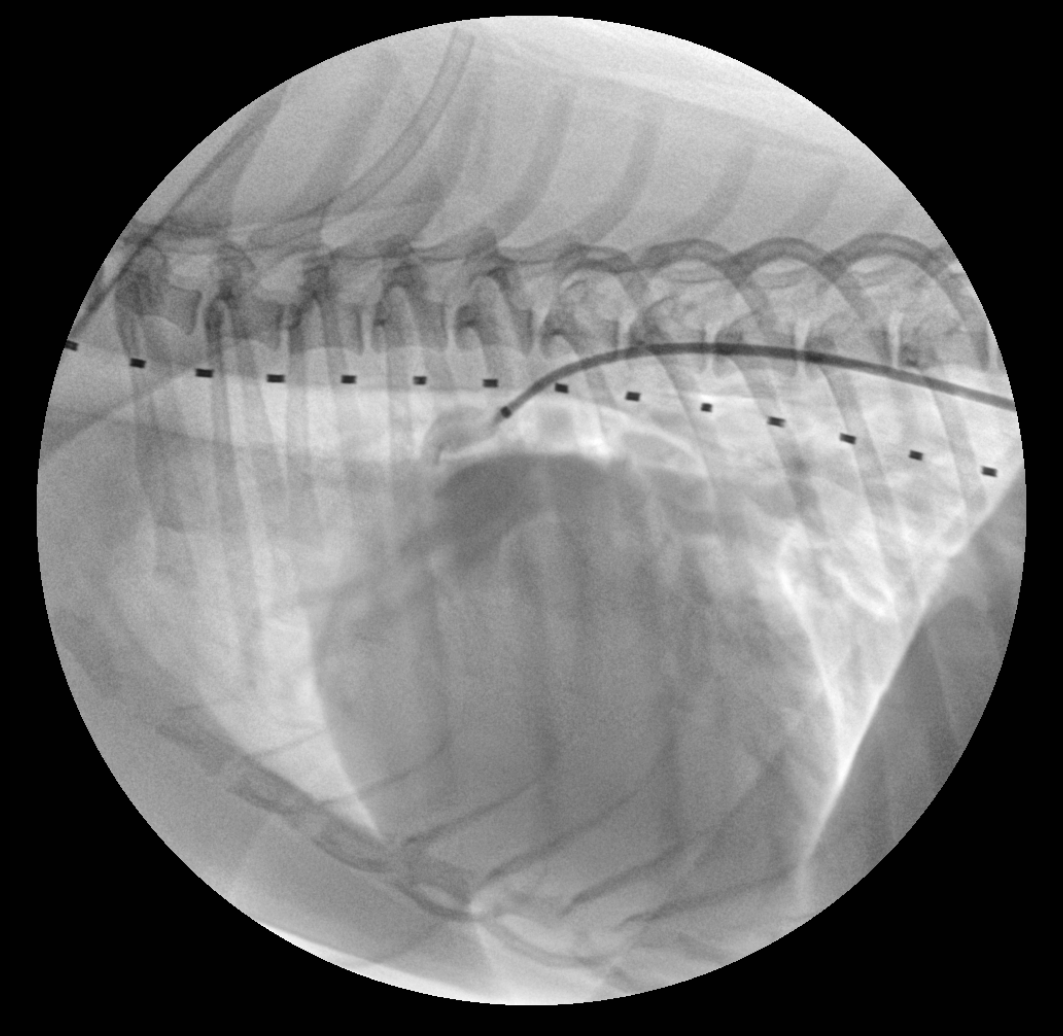

PDA 교정 시술 투시 영상

시술 투시 영상 1

C-arm을 이용한 실시간 투시 영상 가이드 하에 카테터 삽입 과정

시술 투시 영상 2

정확한 위치에 PDA plug 삽입하는 과정의 투시 영상